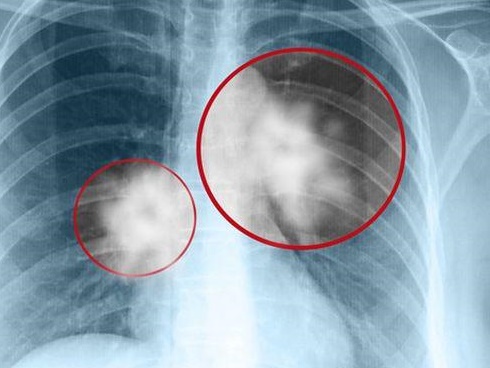

Ban đầu, người phụ nữ đi khám phụ khoa và nghi ngờ bị nhiễm trùng nấm mốc, nhưng không ngờ kết quả cuối cùng cho thấy cô bị ung thư nội mạc tử cung, chỉ có thể cắt bỏ tử cung mới có thể giữ mạng sống. Một thời gian sau, người mẹ lại tiếp tục đưa con gái đang học lớp 3 tới và nói rằng con gái đã có kinh nguyệt nhưng không biết cách thay băng vệ sinh nên đã bị viêm nhiễm phụ khoa.

Ngoài việc điều trị nhiễm trùng cho cả 2 mẹ con, bác sĩ Hong Yongxiang cũng cố gắng tìm hiểu lý do tại sao cả hai mẹ con liên tiếp gặp các vấn đề phụ khoa, mẹ bị ung thư nội mạc tử cung còn con gái lại dậy thì sớm. Sau khi kiểm tra thêm, bác sĩ Hong Yongxiang phát hiện cả 2 mẹ con có nồng độ formate cao gấp 3-5 lần so với bình thường, chứng tỏ thường xuyên tiếp xúc với chất này tại gia đình.

Việc tiếp xúc thường xuyên với chất hóa dẻo trong túi nilon đã gây ảnh hưởng tới sức khỏe. Bất ngờ hơn nữa là ngay cả con trai của người phụ nữ cũng bị ảnh hưởng khi chậm phát triển các dấu hiệu giới tính. Bác sĩ Hong Yongxiang suy đoán rằng chất hóa dẻo có trong túi nilon đã nhiễm vào thức ăn nóng sau đó xâm nhập vào cơ thể, ảnh hưởng tới nội tiết. Do nội tiết tố nữ của cậu con trai đã ức chế nội tiết tố nam nên ảnh hưởng tới sự phát triển của các đặc điểm sinh dục thứ cấp.

Wu Xinjie, một bác sĩ y khoa của Đại học Y North Union, đã từng chỉ ra rằng chất hóa dẻo có thể gây ảnh hưởng tới nội tiết tố nữ. Tiếp xúc lâu dài có thể làm tăng nguy cơ ung thư vú và ung thư nội mạc tử cung ở phụ nữ mang thai. Nồng độ chất chuyển hóa càng cao, nguy cơ bất thường bẩm sinh ở cơ quan sinh sản của các bé trai càng cao.